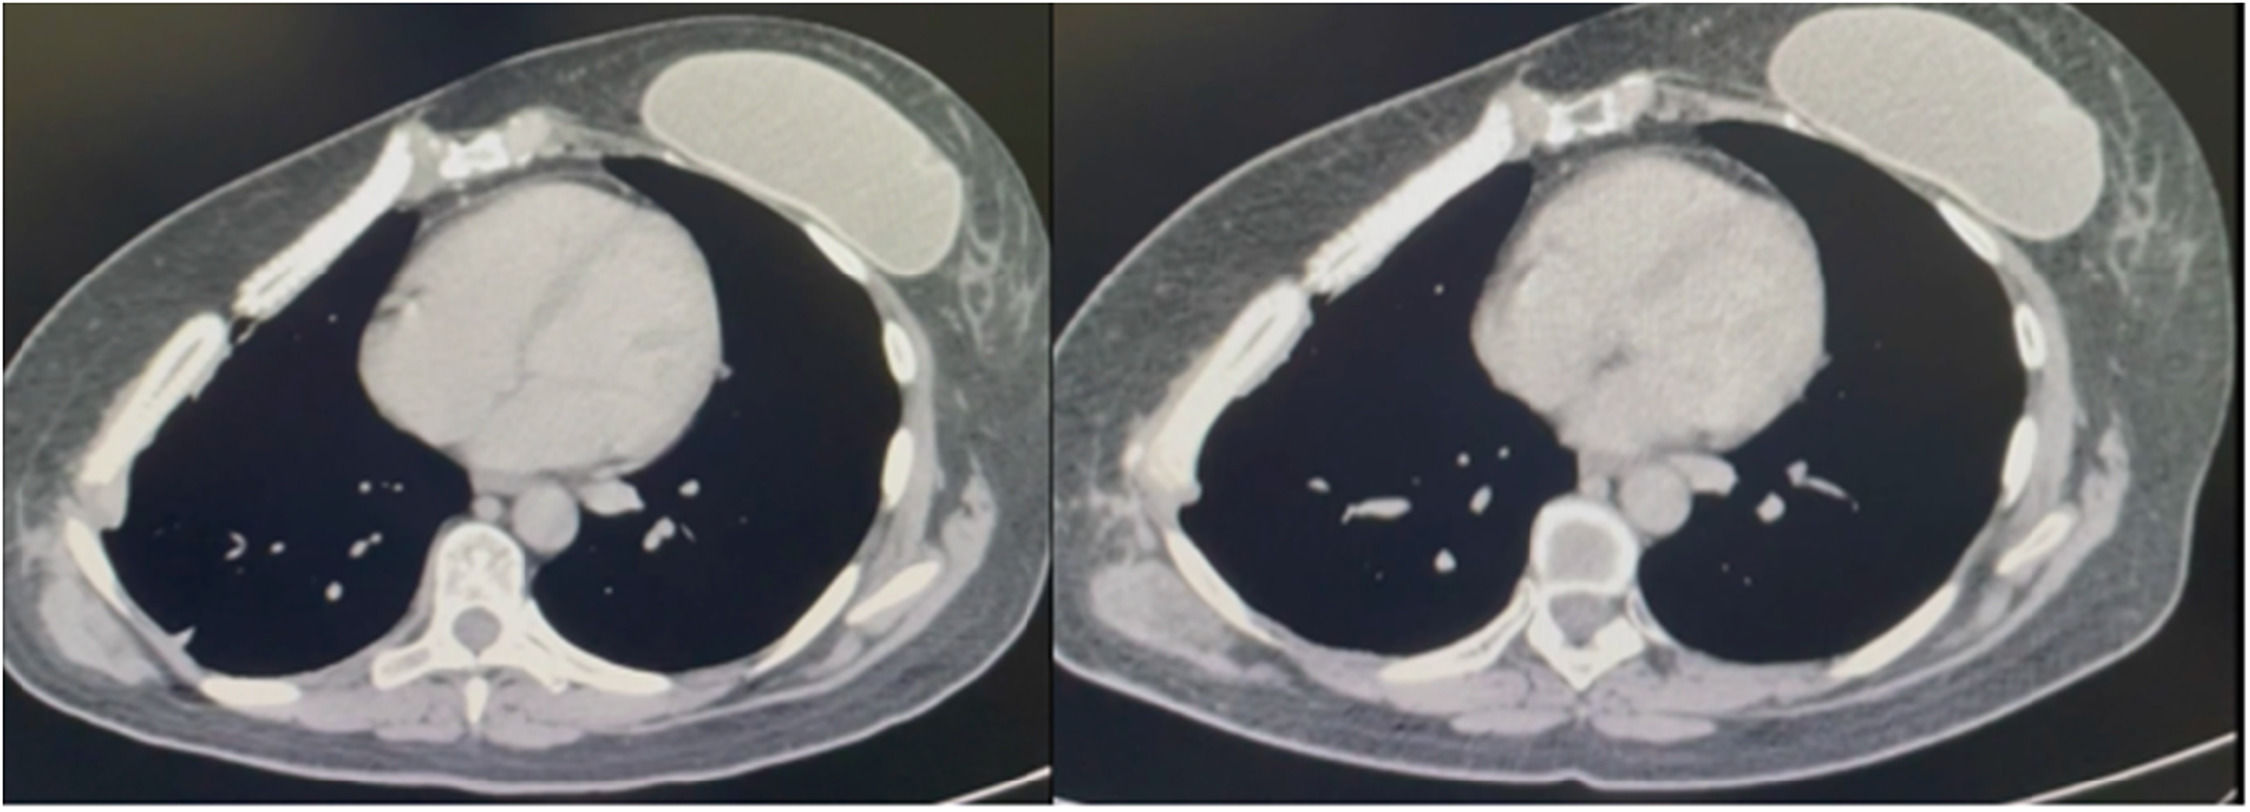

Until now, the three-month postoperative chest tomography has been showing good prosthesis biocompatibility, Fig. 4, and safe use. The wound complication rate is similar to the literature but not related to respiratory failure. The use of this new prosthesis does not seem to increase inflammatory reaction as a consequence of reabsorption and ossification as time goes by. The authors need to increase the sample size and provide further details about the ossification time, especially relating to the size of the resection. The authors continue to collect information for further publications when the study is over.